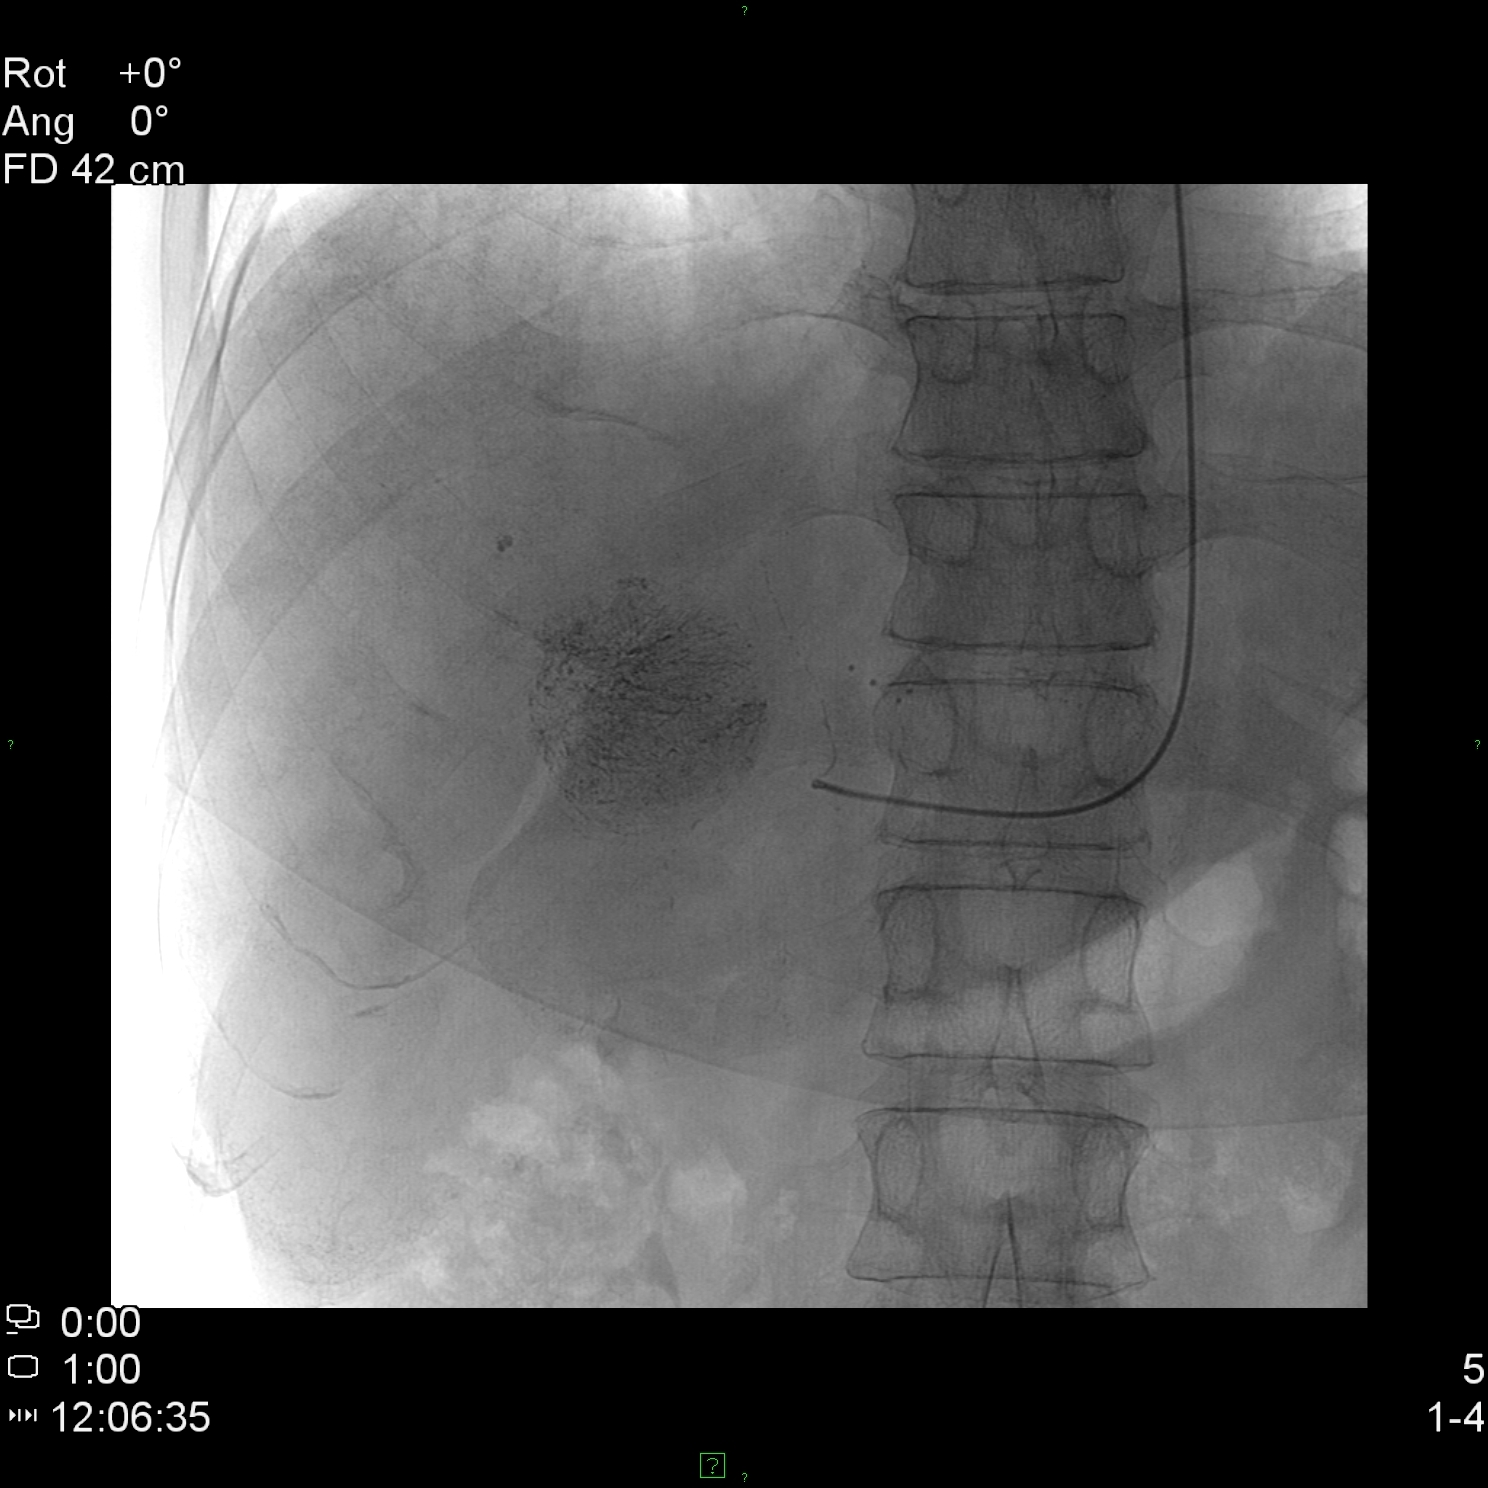

Concerning the HCC, the knowledge of history is very important for the decision and usually the oncoteams consider the performance of an imaging modality guided biopsy basically important for the further therapeutic decisions (because of the hystological validation rather core biopsy should be performed! (Figure 26, 27, 28).

Figure 26: HCC, verified with FNAB, US

Figure 27: HCC, TAE, agniography

Figure 28: HCC, native CT after TAE